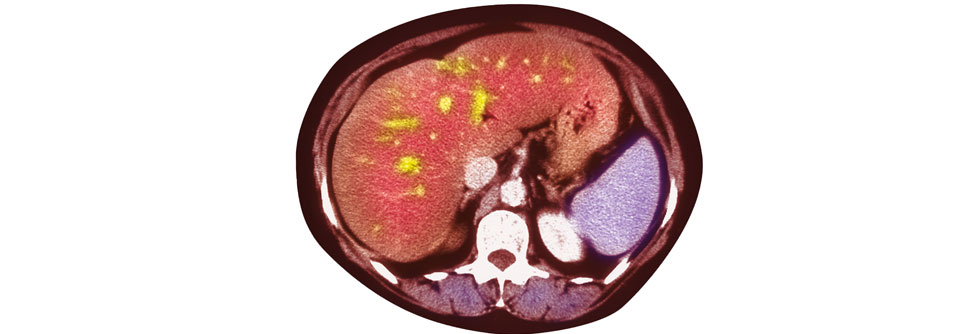

Kohlenhydratarme Kost bringt trotz hoher Gesamtkalorienaufnahme etwas. Kohlenhydratarme Kost bringt trotz hoher Gesamtkalorienaufnahme etwas. © iStock/yulka3ice